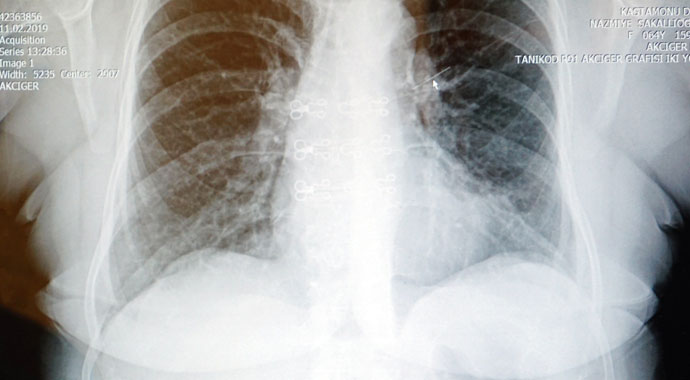

Kastamonu’da Kırkçeşme Mahallesi Muhtarı Tahsin Sakallıoğlu’nun eşi Nazmiye Sakallıoğlu, iki yıl önce eşarbını bağlamak için ağzına aldığı toplu iğneyi yanlışlıkla yuttu. Yuttuğu iğneyi su içerek çıkarmaya çalışan Nazmiye Sakallıoğlu, bunda başarılı olmadı. Öksürük şikayetiyle çeşitli hastanelere başvuruda bulunan Nazmiye Sakallıoğlu, alerjik diye geri gönderildi. Son olarak Kastamonu Devlet Hastanesine müracaatta bulunan Nazmiye Sakallıoğlu, yapılan kontrollerinde akciğerinde 3 santim uzunluğunda toplu iğne olduğu saptandı. Kastamonu Devlet Hastanesi Göğüs Cerrahi Uzmanı Op. Dr. Tarık Yağcı ve ekibi, yaklaşık 1,5 saat süren operasyonla toplu iğneyi bronkoskopi yöntemiyle çıkardı. Akciğerinden toplu iğne çıkartılan Nazmiye Sakallıoğlu ise, öksürüğünün kesildiğini ve kendisini daha iyi hissettiğini söyledi.

Hastanın iki yıldır geçmeyen öksürük şikayetiyle Kastamonu Devlet Hastanesine başvuruda bulunduğunu söyleyen Kastamonu Devlet Hastanesi Göğüs Cerrahi Uzmanı Op. Dr. Tarık Yağcı, “Yabancı cisim aspirasyonları daha çok çocukluk yaş gruplarında karşımıza çıkmakla beraber nadirde olsa yetişkin gruplarında karşımıza çıkabiliyor. Yabancı cisim aspirasyonları herhangi bir semptom vermeyeceği gibi geçmeyen öksürük, hırıltılı soluma, kanlı balgam ve solunumun durmasına da neden olabiliyor. Hastamızda 2 yıldır geçmeyen öksürük şikayeti ile hastanemize başvurmuştu. Yapılan tetkiklerinde sol akciğerde yabancı cisim aspirasyonu şüphesiyle hastaya cilt bronkoskopi uyguladık. Bu cismi bronkoskopi ile kameralı yöntemle açık ameliyata gerek kalmadan iğneyi tamamen çıkarttık. İşlem komplikasyonsuz sonuçlandı ve hastamız sağlığına tekrar kavuştu” dedi.

İğnenin yaklaşık 2,5-3 santim uzunluğunda bir iğne olduğuna dikkat çeken Op. Dr. Yağcı, “Akciğerde kalan yabancı cisimler, akciğerin harap olmasına, kronik akciğer enfeksiyonuna, tekrarlayan zatürreye, kanlı balgamlara neden olabilir. Bunun için hastanın kronik akciğer enfeksiyonundan korunması için yabancı cisimlerin çıkartılması gerekiyor. Yabancı cisim, akciğerde kaldığı sürece yaşamsal tehlikede arz eder. Harekette ve öksürükte etrafındaki ana vasküler damarlara batma ve kanlı balgam riski mevcuttur. Yaklaşık ameliyatımız 1,5 saat kadar sürdü” şeklinde konuştu.